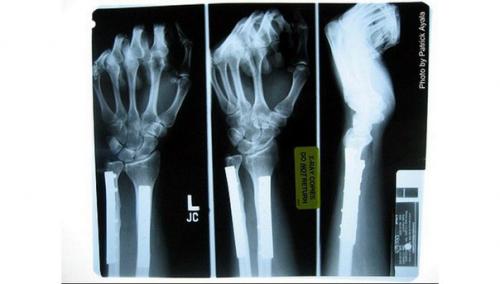

Возрастной остеопороз - заболевание, при котором структура костной ткани с годами ухудшается и становится более хрупкой и уязвимой. Он развивается у более 200 миллионов человек по всему миру. Также подсчитано, что это состояние приводит к 8, 9 миллиона переломов ежегодно. Некоторые из этих переломов ограничивают мобильность пациентов и даже могут привести к смерти. При этом лекарства могут замедлить прогрессирование заболевания, но не излечить его.